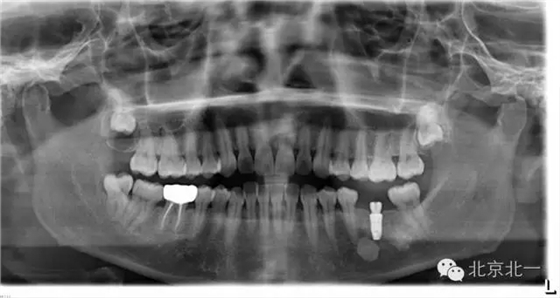

【口腔種植】致密性骨炎/牙骨質(zhì)增生/骨島如何鑒別?

頜骨三種高密度影像的鑒別

1)致密性骨炎

概述:

是指根尖周組織受到輕微緩慢持續(xù)性的低毒性因素刺激,而表現(xiàn)出以骨質(zhì)增生為主的防御性反應(yīng)。一般無自覺癥狀,多見于青年人,下頜第一磨牙多見,常有較大齲壞。

【CBCT表現(xiàn)】:發(fā)生致命性骨炎的環(huán)亞暢游牙體病變,其CBCT表現(xiàn)為圍繞根尖的骨質(zhì)密度增高區(qū),骨小梁增多增粗,骨髓腔變窄甚至消失,與正常骨組織分界不明顯。根尖部牙周膜間隙可增寬,根尖無增粗膨大。

根尖片顯示D6深齲,根尖低密度區(qū)周圍骨小梁增粗、增多,骨質(zhì)密度增高,骨髓腔變?。ê谏^)。

2)牙骨質(zhì)增生:

是由于齲壞、牙周炎、頜創(chuàng)傷等某些局部因素或全身疾患的影響,牙骨質(zhì)形成的異常增加。牙骨質(zhì)增生可發(fā)生于一個或者多個牙,多無臨床癥狀。

【CBCT表現(xiàn)】:

牙骨質(zhì)增生可表現(xiàn)為整個牙根體積的膨大,或僅表現(xiàn)為根尖呈球狀增生,對于多根牙,體積的膨大可局限于個別牙根,不伴根尖周感染的情況下,便便牙牙周膜及硬骨板影像相連續(xù)、完整。部分病例可見牙周膜間隙消失,牙根與牙槽骨粘連,導(dǎo)致牙齒萌出障礙或者滯留。

B6腭根根尖區(qū)膨大,牙周膜和骨硬板消失,根尖周見低密度影,上頜竇下壁骨質(zhì)不連續(xù),B B6頜面已開髓。

3)骨島:

主要和根尖型骨島鑒別,主要集中位于根尖區(qū)的骨島,

在CBCT上,根尖型骨島無低密度帶狀影包繞,與周圍骨質(zhì)分界清晰,具有特征性的毛刷樣邊緣,且其發(fā)生區(qū)域的牙根牙周膜影像連續(xù)、完整、不導(dǎo)致頜骨的膨隆。

右下頜C4根尖區(qū)課件一類圓形高密度影,與周圍骨質(zhì)分界清晰,C4牙周膜影像連續(xù)、完整,下頜骨未見膨隆。